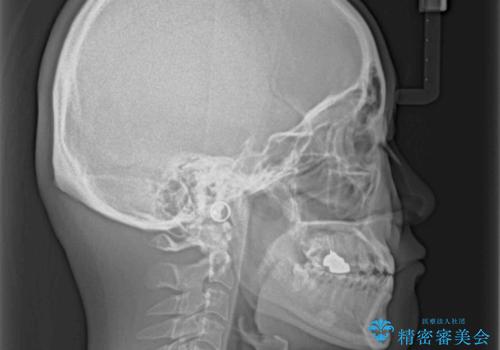

受け口で開咬を急速拡大装置とインビザラインで改善 欠損部分はインプラントにて補綴治療

- 前歯の開咬と、受け口による咬み合わせの悪さを気にして来院された患者様です。

左上は後続永久歯の欠損によりスペースがあり、矯正治療と並行してインプラントあるいはブリッジによる補綴治療が必要な状況でした。

上顎歯列が狭窄していたため、急速拡大装置により上顎骨を側方に拡大し、その後インビザラインにて矯正治療を行うこととしました。